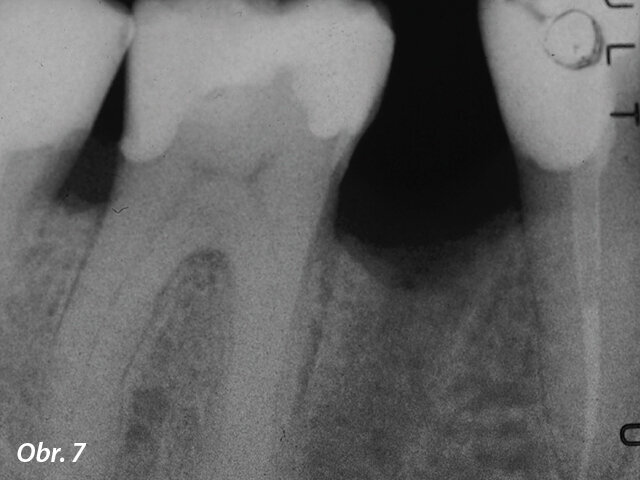

Situace byla zcela odlišná u dolního premoláru na obr. 7–9, kde si při absenci radiologických znaků léze, a i přes zdánlivě správný endodontický přístup jiného kolegy, pacient stěžoval na perzistentní bolest, která byla jak spontánní, tak vyvolaná poklepem. V tomto případě, kdy se zdála být předchozí léčba kořenových kanálků dobrá, by se jako vhodný mohl nabízet chirurgický přístup, který by v takovém případě mohl zajistit vyšší míru úspěšnosti než revize endodontického ošetření. Vzhledem k diagnostickým pochybnostem bylo rozhodnuto zhotovit 3D snímek, který odhalil endodontickou lézi způsobenou neošetřeným lingválním kanálkem. Tato správná diagnóza nám tedy umožnila provést selektivní intervenci na zbylé pulpě vedoucí k úspěšné léčbě neošetřeného kanálku.